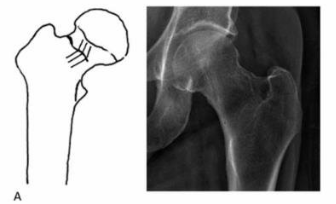

¿Para qué es la clasificación de Pauwels?

Fx intracap femorales por º

Pauwels I

<30º

Mejor pronóstico

Pauwels II

30-70º